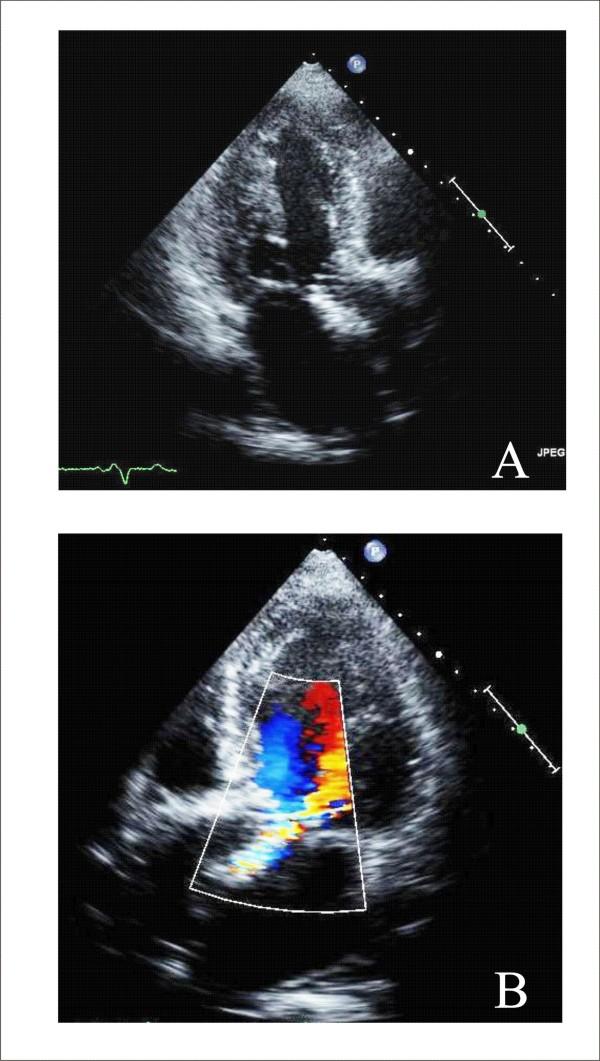

Aortic stenosis and mitral regurgitation, patent foramen ovale, interatrial septal defect, atrial fibrillation and perivalvular leak, are now amenable to percutaneous treatment. These percutaneous procedures require the use of Transthoracic (TTE), Transesophageal (TEE) and/or Intracardiac echocardiography (ICE). This paper provides an overview of the different percutaneous interventions, trying to provide a systematic and comprehensive approach for selection, guidance and follow-up of patients undergoing these procedures, illustrating the key role of 2D echocardiography.

主动脉瓣狭窄、二尖瓣反流、卵圆孔未闭、房间隔缺损、心房颤动及瓣周漏,目前均适合经皮治疗。这些经皮手术需要使用经胸超声心动图(TTE)、经食管超声心动图(TEE)和/或心内超声心动图(ICE)。本文概述了不同的经皮介入治疗,试图为接受这些手术的患者提供一种系统、全面的选择、指导及随访方法,并阐述二维超声心动图的关键作用。